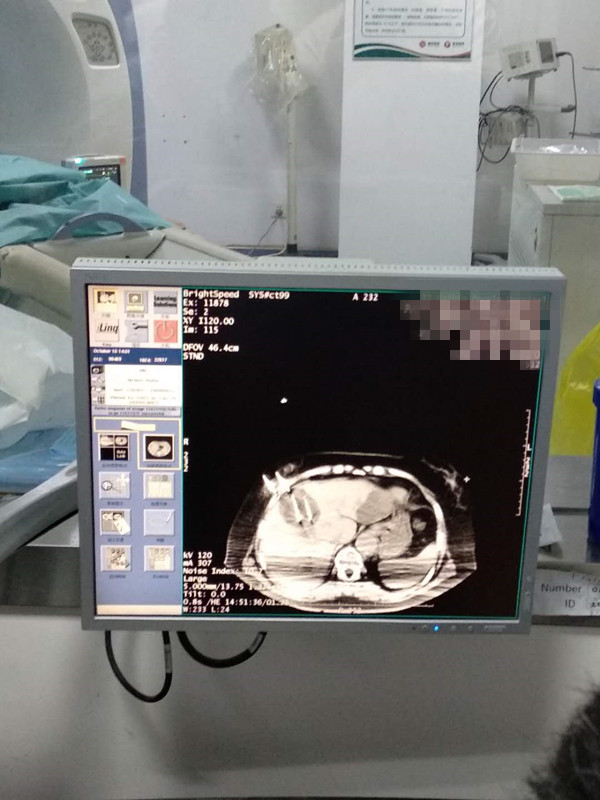

73岁患者肝部氩氦刀冷冻消融

发布人:美国氩氦刀技术官方网站    发布时间:2020/10/16 16:15:21